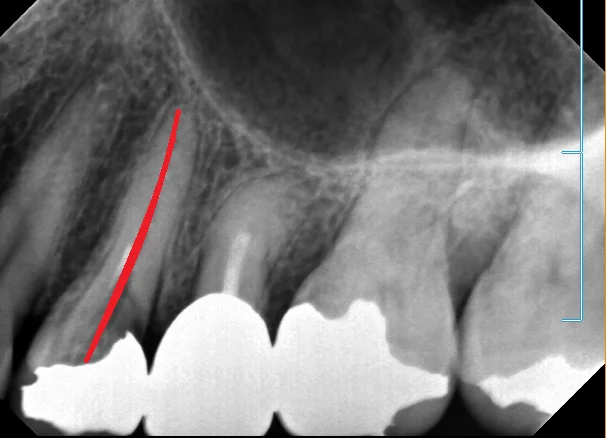

ちなみに、本来あるべき根の形としてはこういったものになるはずなんです。

最初の画像と見比べてもらうと根の管がどれだけ見えづらくなっているのかが分かると思います。